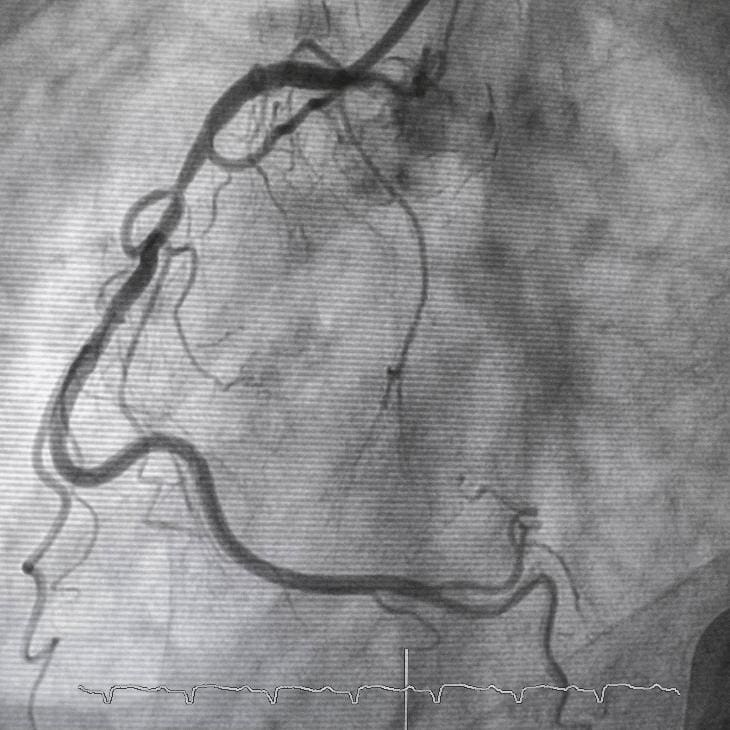

To assess whether high cholesterol has already affected your heart, Dr Sen may recommend investigations such as an echocardiogram, coronary angiography, or advanced imaging. If needed, tests like a cardiopulmonary exercise test (CPET) can evaluate your heart’s performance. Treatment may involve lifestyle changes – such as diet and exercise advice – as well as cholesterol-lowering medication like statins. Dr Sen will clearly explain your results and guide you through a personalised plan aimed at reducing cardiovascular risk safely and effectively.

Angiography